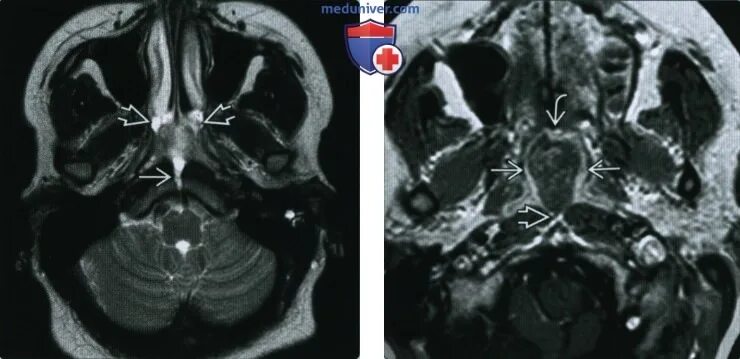

Т2 гипоинтенсивный